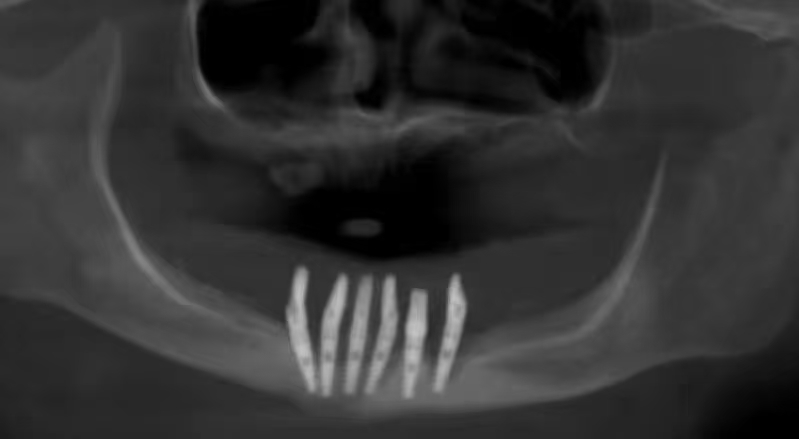

严重的种植并发症一例

严重的种植并发症

触目惊心